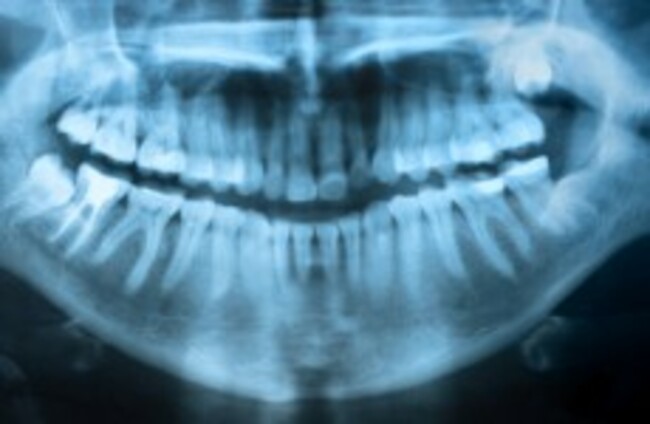

dental records image via Shutterstock

'DNA is sexy' but dental records most useful for identifying bodies

Kerry forensic dentist Paul Keogh told us how his work can help gardaí identify victims and sometimes even the people responsible for crimes.

THE FORENSIC DENTIST who helped identify the body of a German man eight years after his body was found in Connemara has said the public can often be misled about the role DNA plays.

Paul V Keogh helped gardaí identify Arno Schmitz this month using dental records, finally closing the mysterious case from 2006. Speaking to TheJournal.ie this week, he said he had first examined the man’s teeth back in 2006 and could tell straight away that his dentistry was German, even before he’s been told there was any connection to that country.

A forensic dentist, on first looking at a body, can tell from their teeth a number of things like the person’s age, sex and standard of dental work, as well as where it is most likely to have been done. With just 60% of the population of Ireland attending the dentist, however, identification through this method can be difficult – and obviously impossible if the records don’t exist.